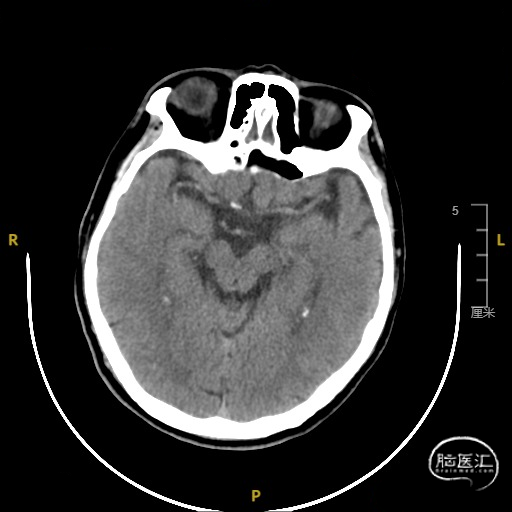

➢ 脑血管造影检查

患者主因言语不利3天入院,头核磁提示右侧额、顶叶多发低灌注梗塞,脑血管造影提示右侧颈内动脉开口重度狭窄,为责任血管,另外患者前交通动脉、右侧后交通动脉开放不良,并且狭窄严重,考虑到高灌注风险,决定分期处理,一期小球囊扩张改善供血,二期支架成型。